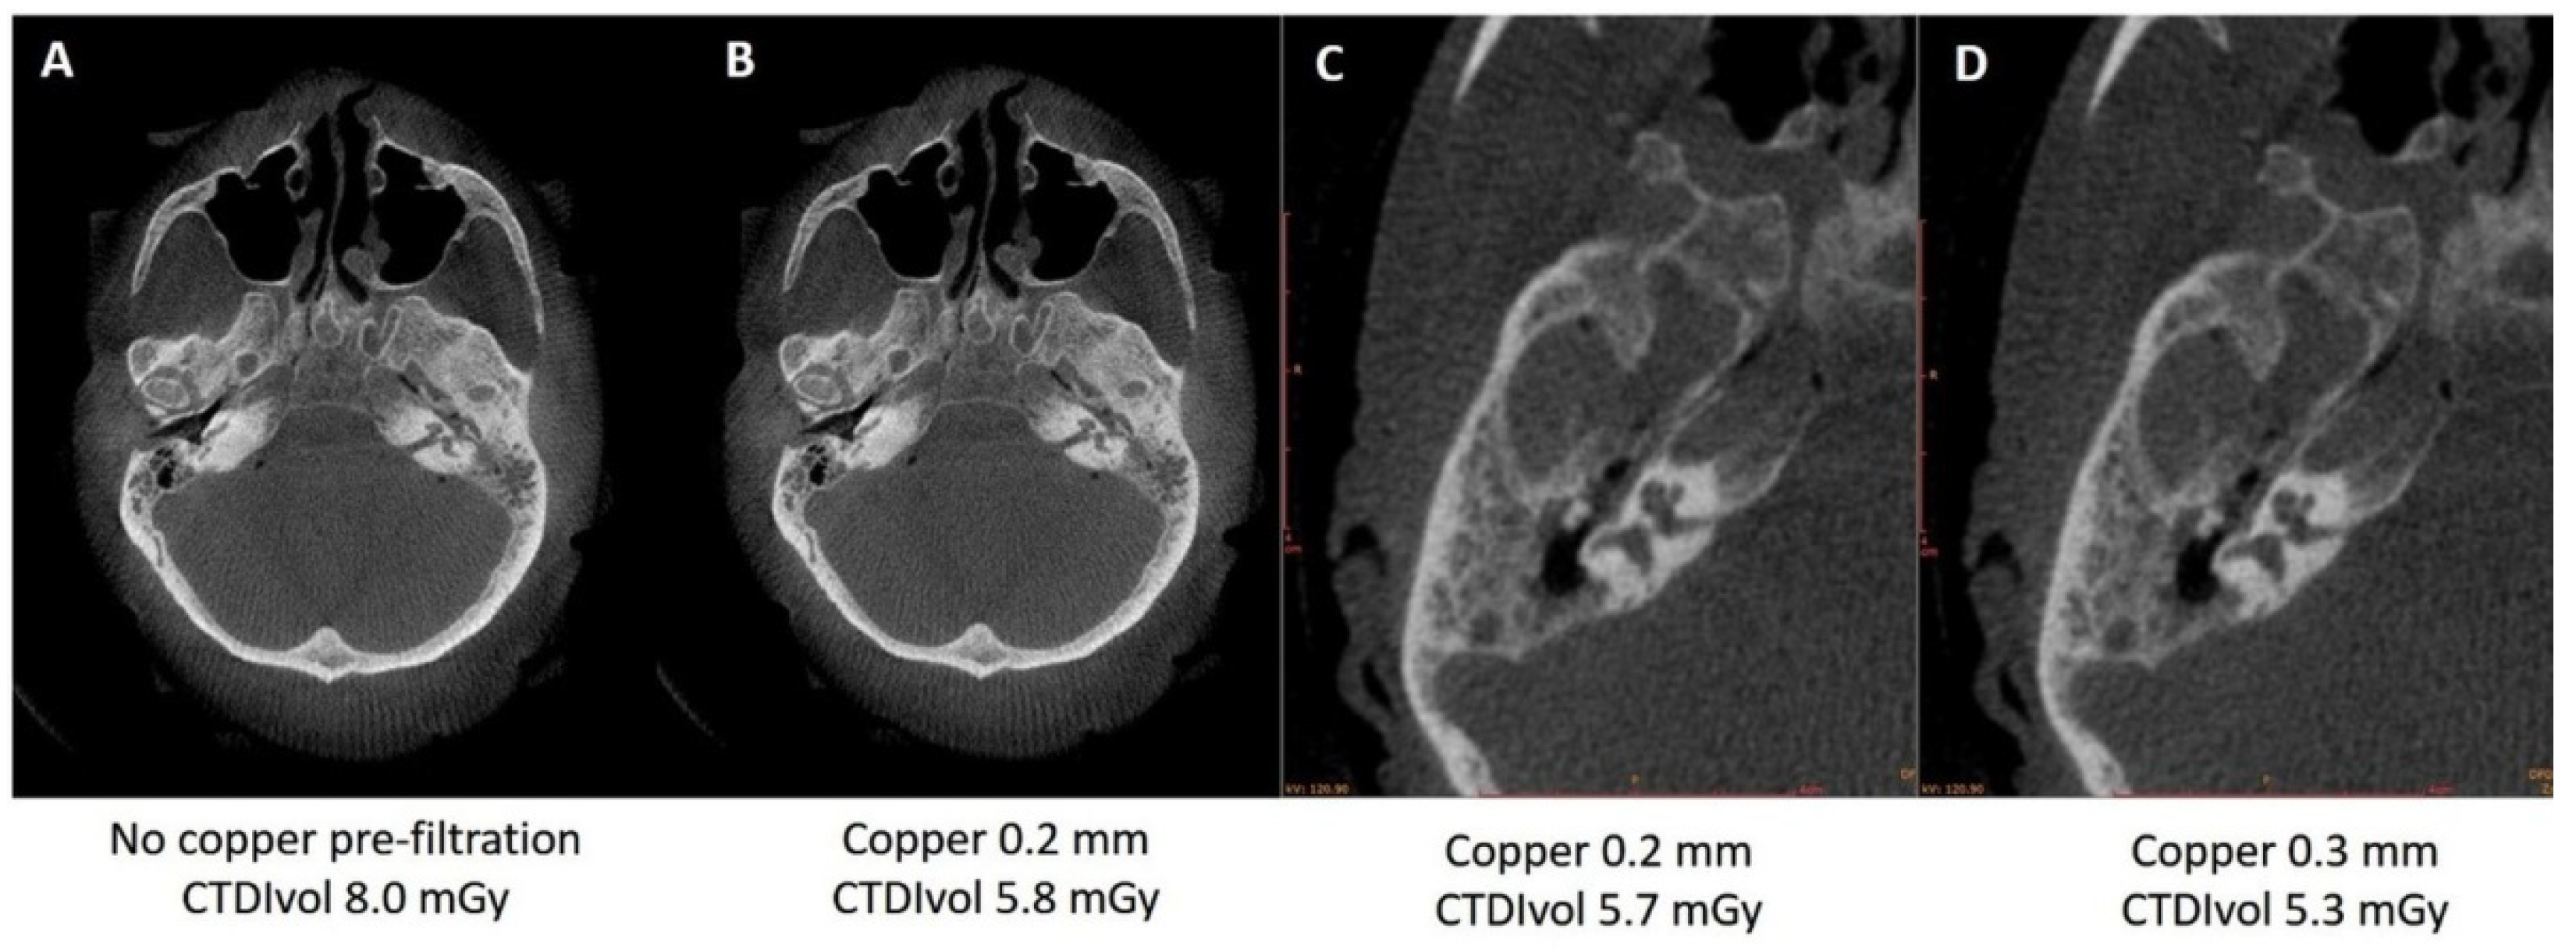

3.2.1. Pre-Filtration with 0.2 vs. 0.3 mm Copper Filter

3.2.2. Pre-Filtration with 0.4 mm Tin Filter